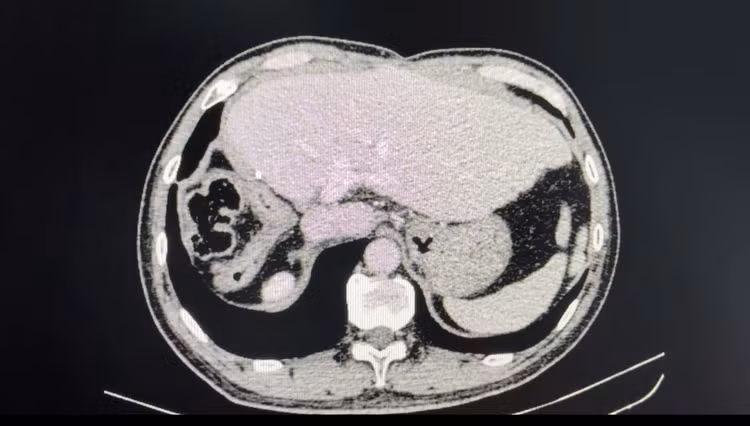

Hình ảnh chụp cắt lớp vi tính sau phẫu thuật 4 năm. Bệnh nhân gan trái tốt, tĩnh mạch cửa thông thoáng, không có tái phát tại gan và di căn xa - Ảnh BVCC